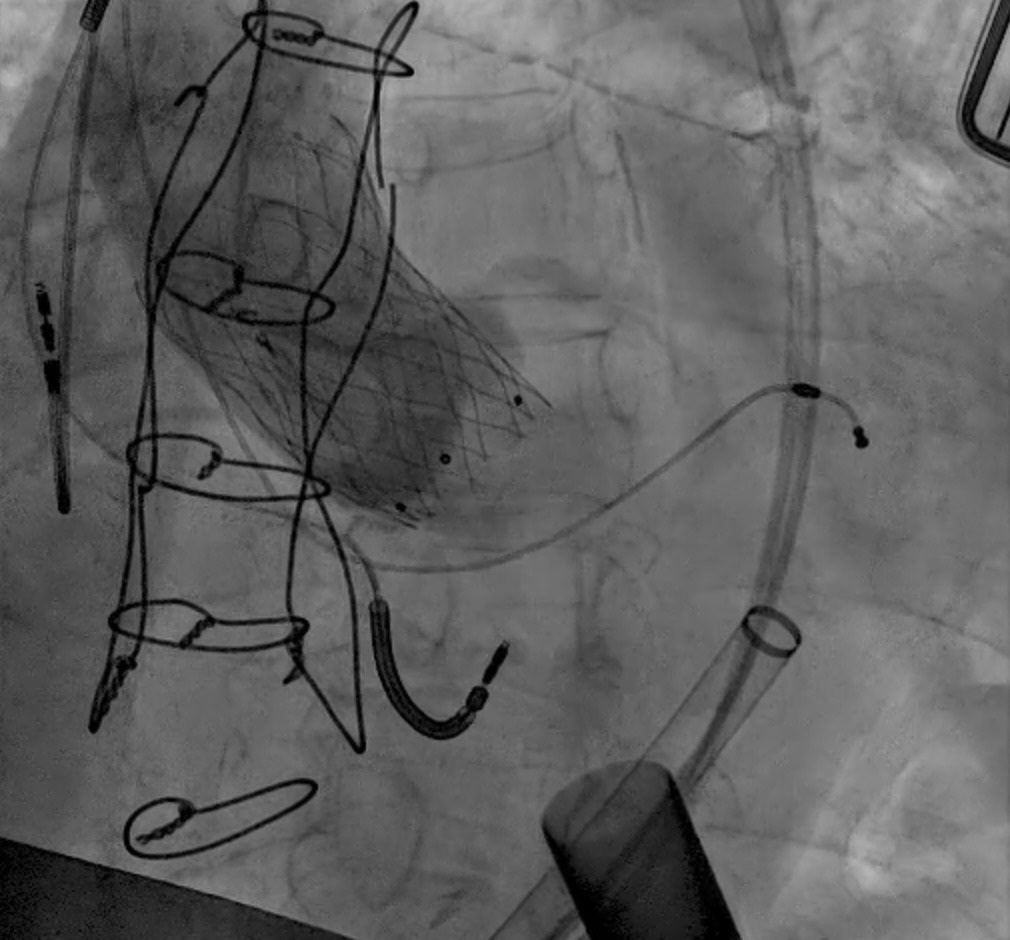

LVAD deactivation can be achieved by surgical explant via median sternotomy or via a hybrid surgical/percutaneous approach described as decommissioning [37]. Complete explant is recommended in younger patients and those with infected drivelines and/or pump. Decommissioning implies retention of the pump within the body. The driveline is cut and buried subcutaneously. The outflow cannula must be occluded to prevent closed loop regurgitant flow from the aorta into the left ventricle, typically with endovascular occlusive device/s at the OFG-ascending aorta anastomosis (Fig. 12). Surgical decommissioning can be achieved minimally invasively and without cardiopulmonary bypass.

Fig. 12. LVAD decommissioning. Outflow cannula occlusion with a series of three large Amplatzer vascular plug 2 (AVP2) from the proximal end to the distal end of the cannula.